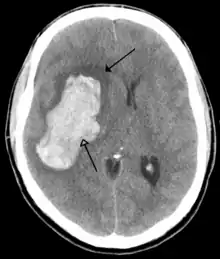

CT scan of an intraparenchymal bleed (bottom arrow) with surrounding edema (top arrow)

There are two main types of hemorrhagic stroke:[28][29]

Strokes can be classified into two major categories: ischemic and hemorrhagic.[18] Ischemic strokes are caused by interruption of the blood supply to the brain, while hemorrhagic strokes result from the rupture of a blood vessel or an abnormal vascular structure. About 87% of strokes are ischemic, the rest being hemorrhagic. Bleeding can develop inside areas of ischemia, a condition known as "hemorrhagic transformation." It is unknown how many hemorrhagic strokes actually start as ischemic strokes.[2]